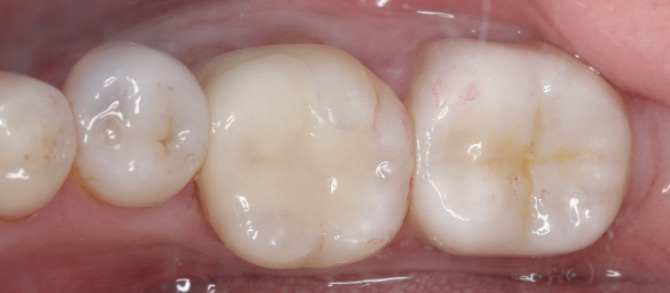

修复后,患者的牙齿不仅外观自然,咀嚼功能也完全恢复。嵌体修复因其密合性好、耐用性强,能有效防止继发龋的发生。患者表示,嵌体修复不仅解决了他的牙齿问题,还让他更加重视日常口腔护理。

嵌体修复是治疗龋坏牙齿的理想选择,既美观又实用,帮助患者重拾健康笑容!